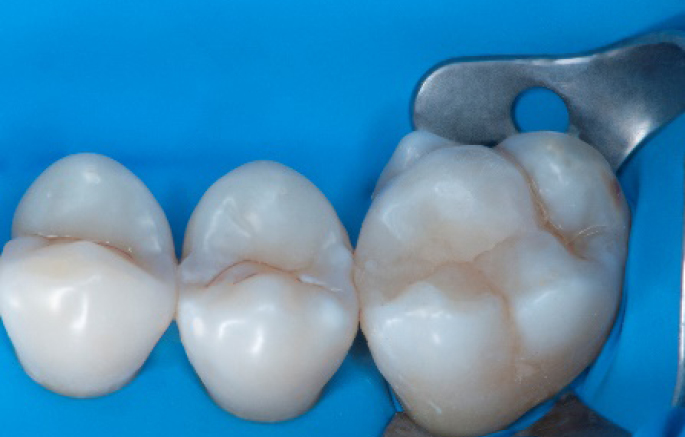

Step 1:

The situation after rubber dam isolation.